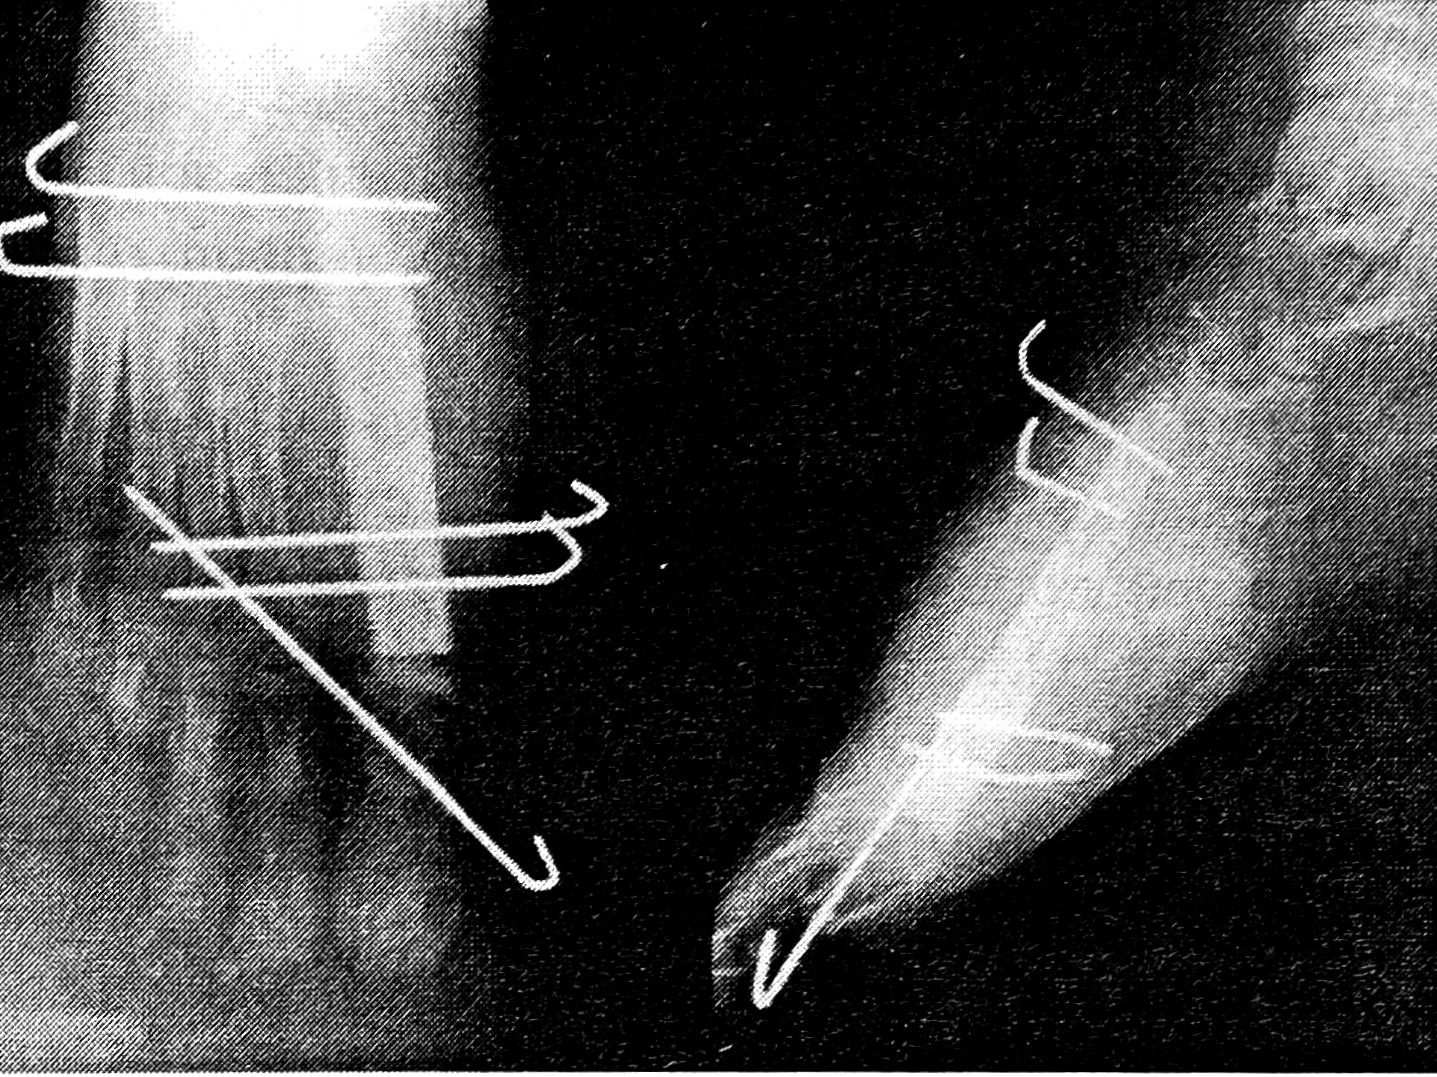

Больная К., 13 лет, поступила в ЦИТО по поводу тотального дефекта I плюсневой кости правой стопы вследствие посттравматического остеомиелита и неоднократных секвестрэктомий, с жалобами на затрудненную ходьбу и нарастающую деформацию I пальца (рис. 1). Первым этапом на I луч стопы был наложен стержневой компрессионно-дистракционный аппарат, с помощью которого создан диастаз на длину пястной кости между клиновидной костью и основной фалангой пальца (рис. 2). После этого 19.09.95 под общим обезболиванием двумя бригадами хирургов произведены замещение дефекта плюсневой кости свободным васкуляризированным малоберцовым трансплантатом, эндопротезирование плюснефалангового сустава силиконовым эндопротезом, пластика дефекта кожи полнослойным кожным трансплантатом (рис. 3). Одна бригада хирургов иссекла рубцы по внутренней поверхности стопы, выделила для наложения микрососудистых анастомозов заднюю большеберцовую артерию и сопровождающие ее вены, подготовила ложе для костного трансплантата. Вторая бригада в это время производила забор малоберцового костного трансплантата длиной 9,5 см с питающей его артерией и венами, мышечной муфтой толщиной 0,8 см. Затем костный трансплантат был адаптирован на стопе и фиксирован к соседним костям спицами Киршнера (рис. 4). Перед выполнением остеосинтеза на дистальный конец трансплантата был «надет» соответствующего размера силиконовый эндопротез, предназначенный для замещения головки плюсневой кости. Наложены микроанастомозы между артерией костного трансплантата и задней большеберцовой артерией и сопровождающими их венами. После снятия сосудистых клипсов отмечено обильное капиллярное кровотечение из мышечной муфты, свидетельствующее о хорошей проходимости сосудистых микроанастомозов и кровообращении в трансплантате. (Последнее было многократно подтверждено в разные сроки послеоперационного периода допплерографически.) На рану наложены послойные швы. Оставшийся кожный дефект размером 1,2 × 4 см закрыт полнослойным кожным аутотрансплантатом. Наложены асептическая повязка и задняя гипсовая лонгета с фиксацией стопы в положении, исключающем малейшее натяжение микрососудистых анастомозов.

Рис. 2. Рентгенограммы правой стопы со стержневым аппаратом перед операцией.